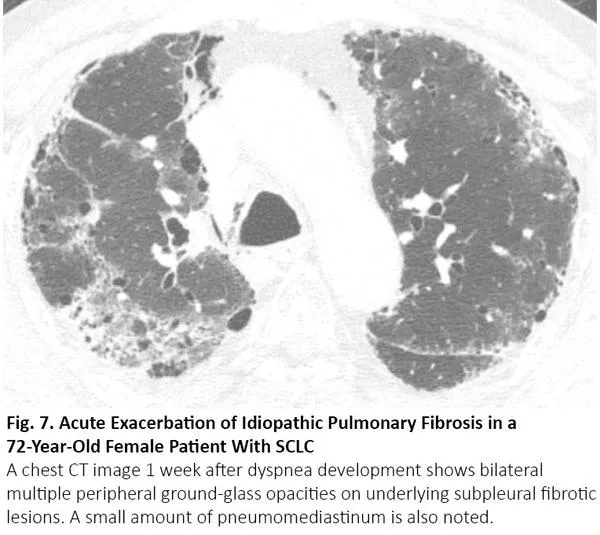

COVID-19患者的肺部CT的典型表现为双侧多发磨玻璃样影,好发于肺周3(图1)。61%~72%的COVID-19患者在症状出现后1周左右有典型CT表现,而非COVID-19患者只有不到10%人群有此类表现。4,5

图1. COVID-19患者胸部CT的典型表现

COVID-19的胸部CT可伴有局部的实质化和网状阴影(铺路石征影像表现)或其他组织性肺炎的表现,如反晕征。17% - 20%的COVID-19患者的CT与各种感染性、非感染性肺部疾病(如超敏性肺炎、肺孢子虫肺炎和弥漫性肺泡出血)难以区分(图2)。